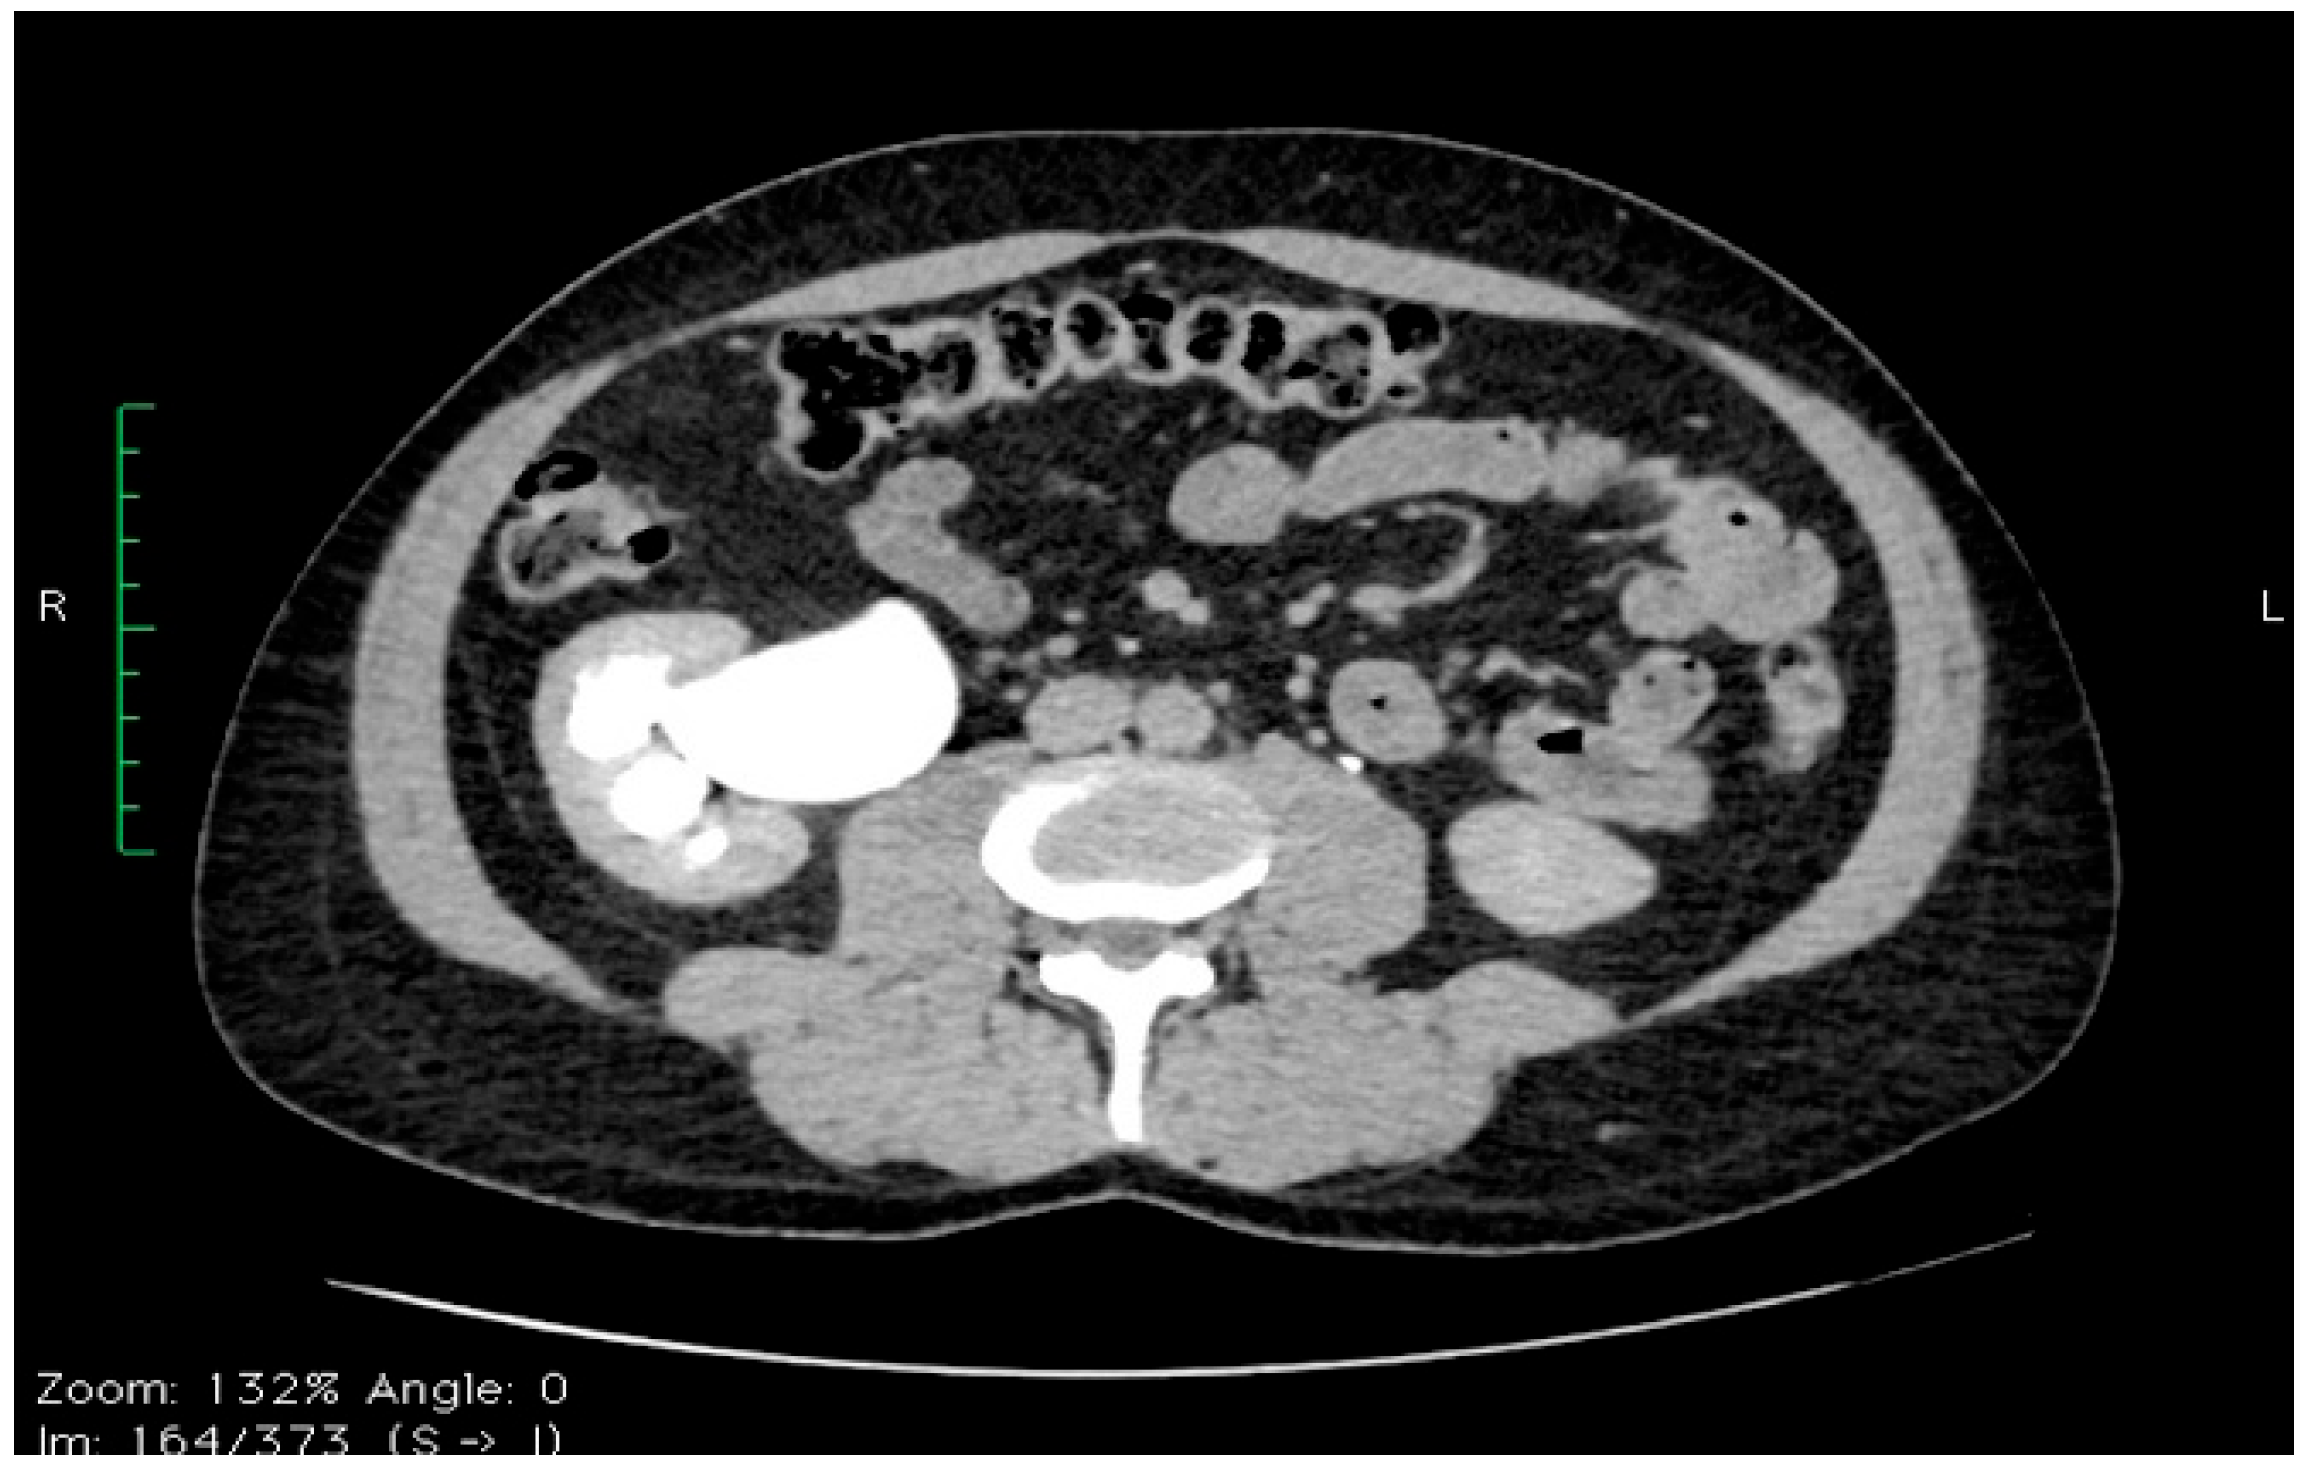

2. Case Report